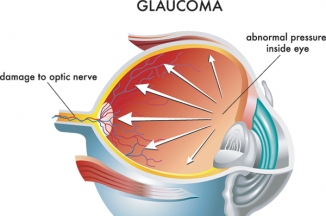

გლაუკომის სამკურნალოდ გამოყენებული ხალხური საშუალებები!

გლაუკომა თვალის მძიმე ქრონიკული დაავადება, რომლის ძირითადი ნიშნებია თვალშიგა წნევის მომატება და მხედველობის დაქვეითება. წნევის მომატებას იწვევს..